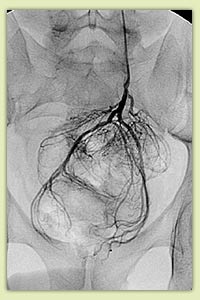

|

Варикоцеле: патологический кровоток по семенной вене (А); окклюзия вены через 30 мин после введения склерозанта (Б) |